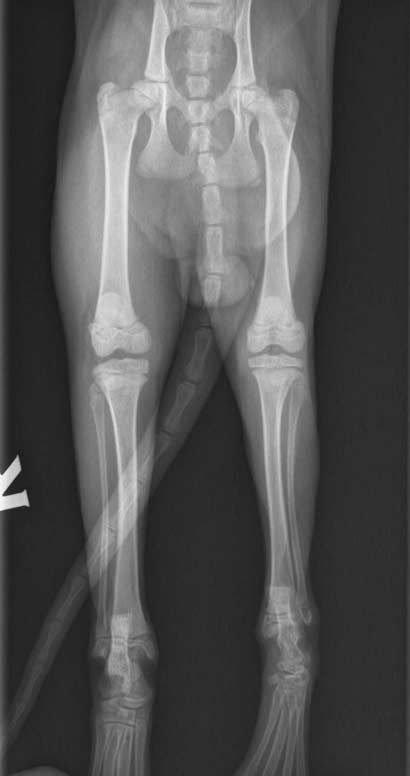

Luke im Januar 2015 nach der OP:

Luke wurde der Fixateur entfernt

Luke wurde in die Tierklinik gebracht und sein Fixateur konnte nun entfernt werden.

Nun darf der kleine Kerl wieder spielen und uneingeschränkt mit seinen Spielkameraden springen und toben. Das genießt er sehr und belastet nun auch das "kranke" Bein wieder - was er auch soll.

Zur vollständigen Genesung benötigt Luke nun Phyiotherapieübungen, um die Beweglichkeit und Beugung seines Beines komplett wieder herzustellen.

Luke wurde in der chirurgischen Klinik operiert und es geht dem Kleinen den Umständen entsprechend gut. Sein Bein wurde mit einer Platte und einem Fixateur externe versorgt und er durfte noch am gleichen Tag die Klinik verlassen.

Wir brachten ihn in eine Chirurgische Klinik, wo er eingehend untersucht und geröntgt wurde.

Bei Luke wurde eine mehrfache Achsen-Fehlstellung im linken Hinterlauf diagnostiziert, vermutlich hatte er als Katzenbaby einen Unfall.

Dies kann nicht mehr nachvollzogen werden, aber Luke kann operiert und das Bein erhalten werden.

Luke vor der OP